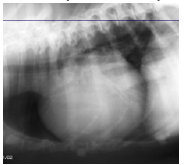

DCM